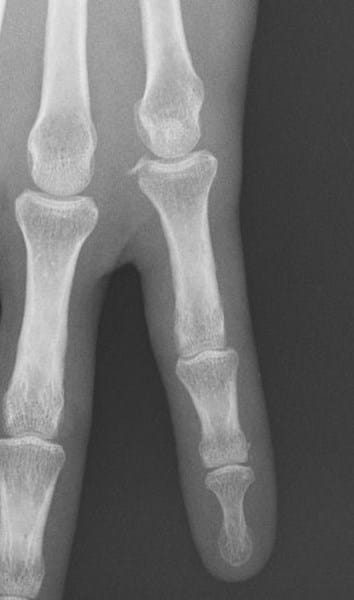

Tras caída corriendo, siento dolor en el meñique. El trauma mandó RX, pero no apreció nada; a mí me parece que hay algo

Es en el nudillo del meñique de la mano izquierda. Parece como si se hubiera desprendido un trocito de hueso.

Me pasó hace dos semanas y sigo con un poco de inflamación y me duele al cerrar la mano.